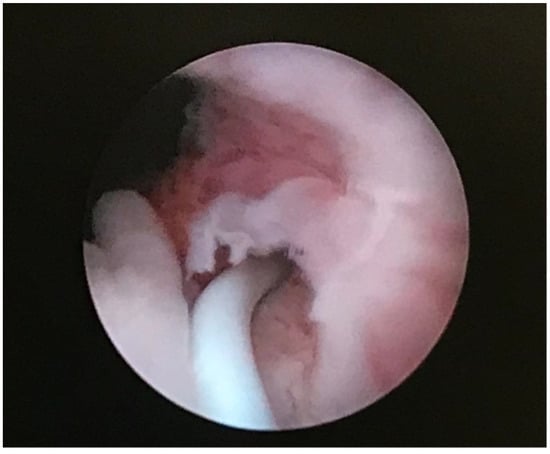

2.1. Case Study No. 1

2.2. Case Study No. 2